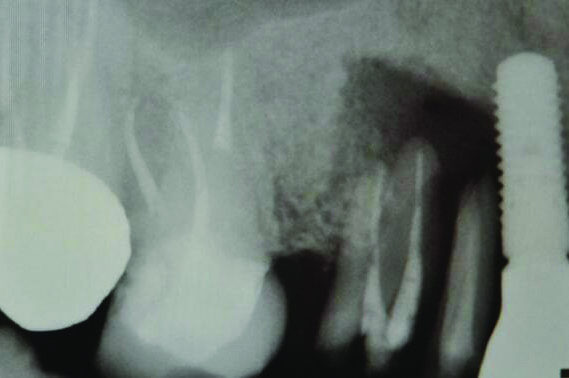

Fig 3 and Fig 4. Case 2: Initial clinical presentation showing implant No. 6 with RPI, having been impacted by fractured tooth No. 5 (Fig 3); radiograph showing fractured tooth No. 5 with periapical lesion extending to the distal aspect of implant No. 6 (Fig 4).

Fig 4. Case 2: Initial clinical presentation showing implant No. 6 with RPI, having been impacted by fractured tooth No. 5 (Fig 3); radiograph showing fractured tooth No. 5 with periapical lesion extending to the distal aspect of implant No. 6 (Fig 4).

Figure 4

Patient 2: A 63-year-old healthy male patient presented with implant No. 6 exhibiting RPI, having been affected by previously endodontically treated and fractured tooth No. 5 (Figure 3 and Figure 4). The implant had probing depths ranging from 4 mm to 10 mm (Table 1) with the most severe bone loss at the distal aspect of implant No. 6 (Figure 3 and Figure 4).